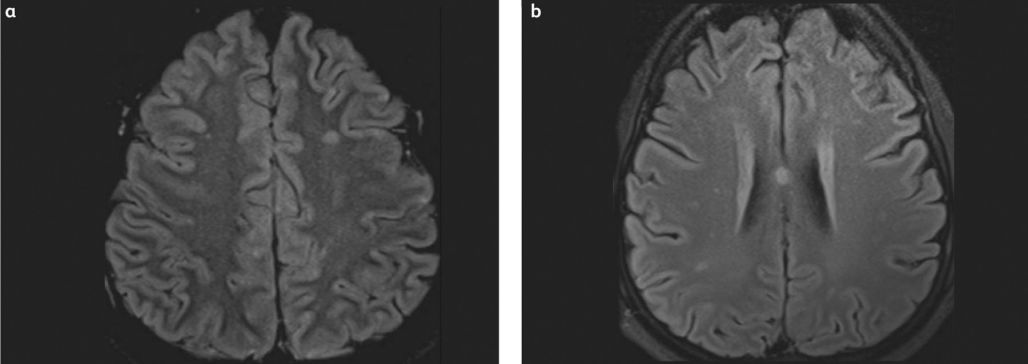

Imaging Studies

Magnetic resonance imaging (MRI) typically reveals multiple small (2 to 7 mm) hyperintense lesions (Figure 3) on T2-weighted images, most commonly located in the subcortical and deep white matter, periventricular regions, and corpus callosum.[5][14]